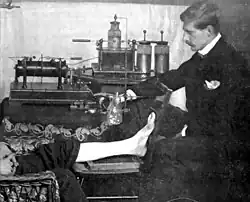

Rowland's career began in medical journalism while he was still a medical student when, in 1896, as Hart's intern, the year following the discovery of X-rays,[6] the BMJ appointed Rowland as "Special Commissioner" to produce a report on the clinical use of X-rays titled "Report on the Application of the New Photography in Medicine and Surgery."[3][6][a] It was published in 17 parts between 8 February 1896 and 12 June 1897.[3] In May 1896, he founded the world's first X-ray journal, the Archives of Clinical Skiagraph, a radiology journal that preceded the British Journal of Radiology.[3][6] In the preface to the first issue, written in April 1896, he wrote that "the object of this publication is to put on record in permanent form some sort of the most striking applications of the new photography to the needs of medicine and surgery".[6] He coined the term "skiagraphy" to describe the making of X-ray pictures and wrote some of the early works on radiology.[3] Without any radiology experts or X-ray departments at the time, his journal became an essential reading.[6]